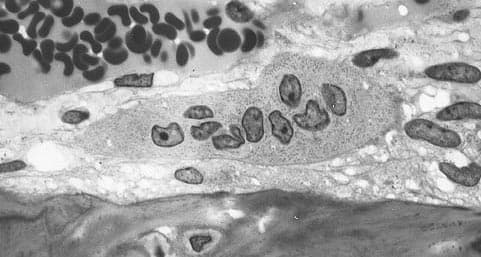

An osteoclast () is a type of bone cell that breaks down bone tissue. This function is critical in the maintenance, repair, and remodeling of bones of the vertebral skeleton. The osteoclast disassembles and digests the composite of hydrated protein and mineral at a molecular level by secreting acid and a collagenase, a process known as bone resorption. This process also helps regulate the level of blood calcium. Osteoclasts are found on those surfaces of bone that are undergoing resorption. On such surfaces, the osteoclasts are seen to be located in shallow depressions called resorption bays (Howship's lacunae). The resorption bays are created by the erosive action of osteoclasts on the underlying bone. The border of the lower part of an osteoclast exhibits finger-like processes due to the presence of deep infoldings of the cell membrane; this border is called ruffled border. The ruffled border lies in contact with the bone surface within a resorption bay. The periphery of the ruffled border is surrounded by a ring-like zone of cytoplasm which is devoid of cell organelles but is rich in actin filaments. This zone is called clear zone or sealing zone. The actin filaments enable the cell membrane surrounding the sealing zone to be anchored firmly to the bony wall of Howship's lacunae. In this way, a closed subosteoclastic compartment is created between the ruffled border and the bone that is undergoing resorption. The osteoclasts secrete hydrogen ions, collagenase, cathepsin K and hydrolytic enzymes into this compartment. Resorption of bone matrix by the osteoclasts involves two steps: (1) dissolution of inorganic components (minerals), and (2) digestion of organic component of the bone matrix. The osteoclasts pump hydrogen ions into subosteoclastic compartment and thus create an acidic microenvironment, which increases solubility of bone mineral, resulting in the release and re-entry of bone minerals into the cytoplasm of osteoclasts to be delivered to nearby capillaries.